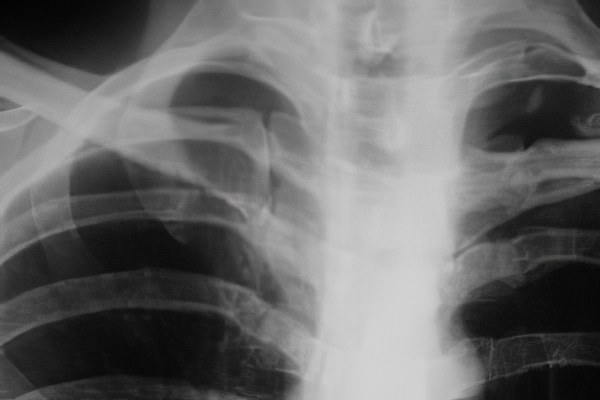

В современной медицине для диагностики переломов ребер используются рентгенография, магнитно-резонансная томография (МРТ) и компьютерная томография (КТ). Сначала выполняется рентгеновский снимок, который часто достаточно для выявления очевидных и простых переломов. Если рентген не дает четкой картины или не позволяет определить степень и местоположение повреждения, рекомендуется использовать МРТ и КТ. Эти методы помогают точно установить характер травм как ребер, так и окружающих мягких тканей и сосудов.